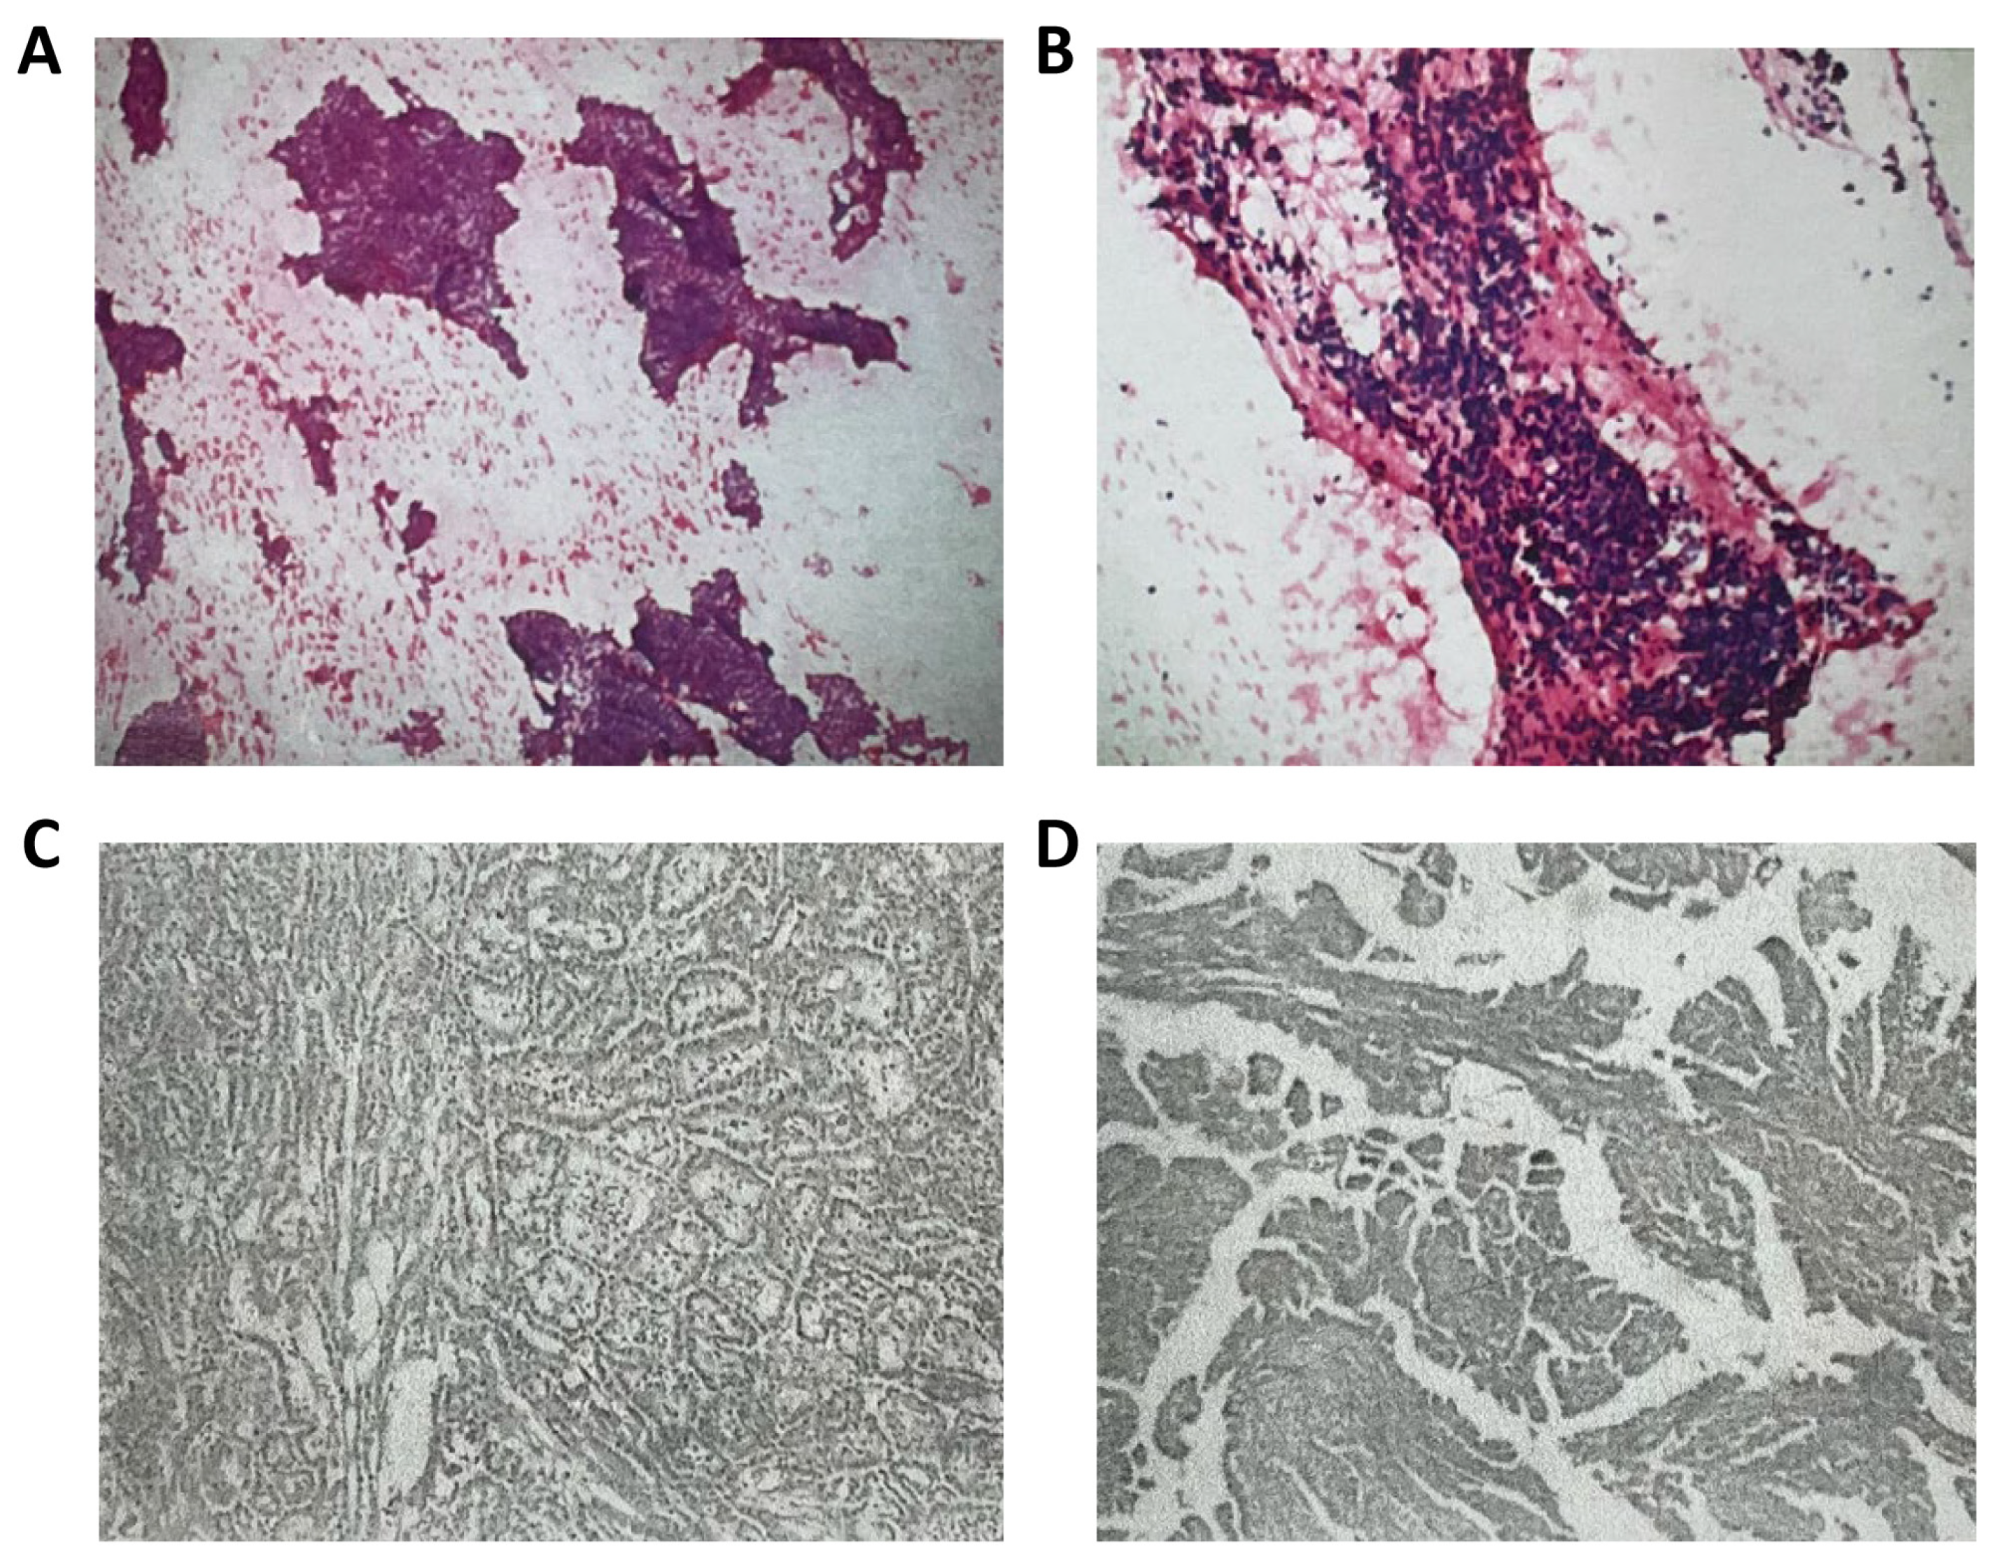

| July 2024 | Surgical resection |

| Pathology: considered aggressive B-cell non-Hodgkin’s lymphoma | |